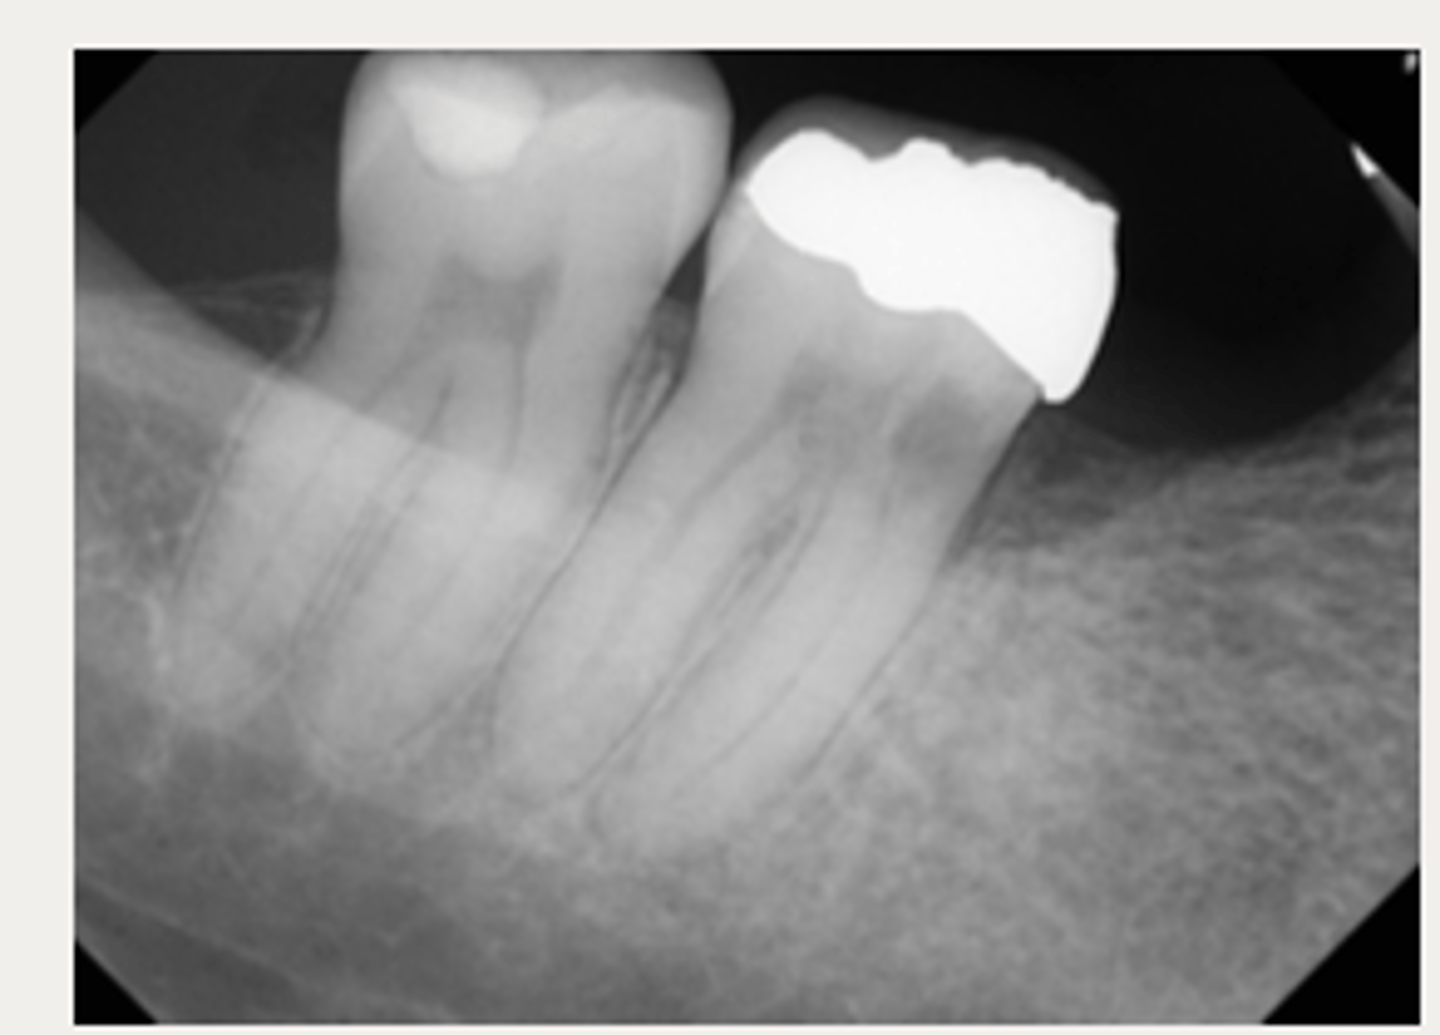

External Replacement Resorption/Ankylosis

Which type of resorption?

- Fusion of cementum or dentin with alveolar bone

Which type of resorption>

- Damage to PDL ⇒ stimulus for surrounding bone to activate osteoclasts and begin resorbing cementum/dentin and replacing it with bone tissue

- Almost always due to trauma (luxation, intrustion, avulsion, replantation)

ID the type of resorption:

CLINICAL

- Characteristic metallic sound on percussion

- May appear infraoccluded in developing dentition

- Lacks physiologic mobility of normal teeth

- May not respond to sensibility testing

RADIOGRAPHIC

- Absence of lamina dura/PDL

- Bone trabeculation occupying previous root surface

- CBCT is often helpful to assess the full extent

Patient presents with these radiographic findings. What is the most likely diagnosis?

- Absence of lamina dura/PDL around lesion.

- Bone trabeculation occupying previous root surface.